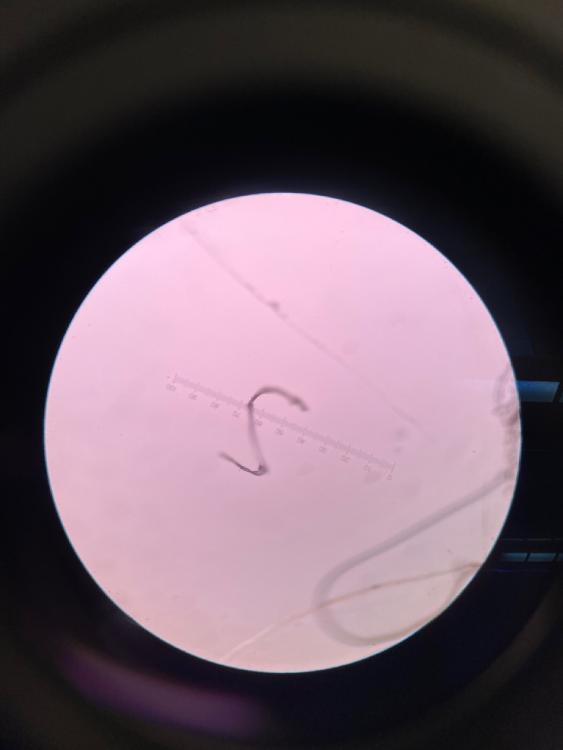

Necator larvae

Strongyloides larvae